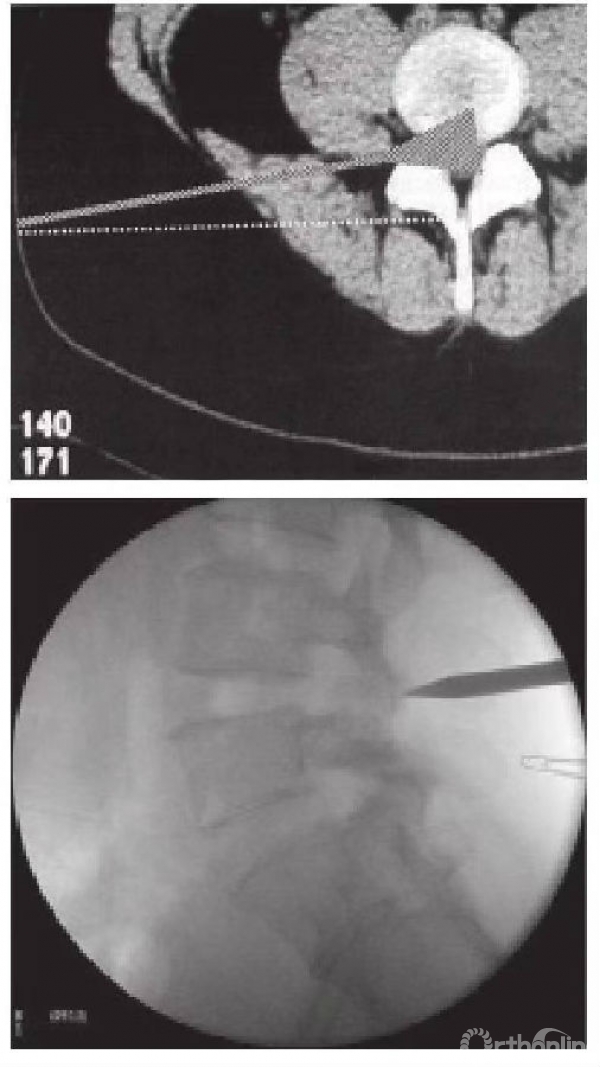

第三个是靶向椎间盘摘除术,由德国医师Hoogland研发,属于直接到目标病灶区域进行减压的手术方式(图5)。由于这个直接标靶理念的改变,大大提升了手术的成功率及普遍性。同时由于这个理念的推广及应用,使得内镜用于治疗腰椎间盘突出成功率大大提升,其也是目前使用最普遍的脊柱微创手术方式。

图5 标靶性椎盘摘除术